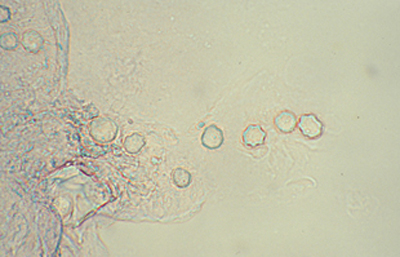

El examen de las perparaciones sin colorear en campo claro y bajo Contraste de Fases también permite una buena visualización de las formas quísticas de Acanthamoeba. (Figura 35)

Fig. 34 Contraste de fase. Original x160

En nuestra práctica empleamos usualmente el Contraste de Fases, el Blanco de Calcofluor, la coloración de Giemsa, y frecuentemente la de PAS. Las tres primeras son más sencillas y rápidas y pueden practicarse en un mismo extendido. Estas técnicas y coloraciones son las mismas que empleamos para el estudio de extendidos en queratitis micóticas.